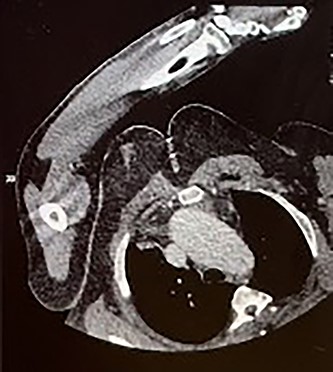

Four months later, the patient developed dyspnoea and orthopnoea. He was also found to be positive for COVID-19. He was clinically well and his hepatitis C viral load was undetectable. A CT aorta-thorax demonstrated that the ascending aorta had further dilated (60 × 61 mm). This aneurysm compressed the trachea resulting in his acute respiratory symptoms (Fig. 3). The patient was diagnosed with an acute-on-chronic type A aortic dissection with mild–moderate aortic regurgitation. Emergency thoracic aortic surgery was performed with remodelling of the sinotubular junction with a prosthetic graft and aortic valve repair. The patient had a long post-operative recovery phase complicated primarily due to his COVID-19 diagnosis. He was discharged 43 days after his surgery.

CT aorta thorax on patient’s re-admission four months later. Ascending aortic aneurysm has increased in size (measuring 60 × 61 mm) compressing the trachea.